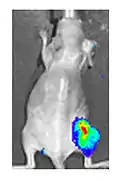

Both in the laboratory and in the clinic it is useful to have a simple means of identifying cells infected by the experimental virus. This can be done by equipping the virus with "reporter genes" not normally present in viral genomes, which encode easily identifiable protein markers. One example of such proteins is GFP (green fluorescent protein) which, when present in infected cells, will cause a fluorescent green light to be emitted when stimulated by blue light.[81][82] An advantage of this method is that it can be used on live cells and in patients with superficial infected lesions, it enables rapid non-invasive confirmation of viral infection.[83] Another example of a visual marker useful in living cells is luciferase, an enzyme from the firefly which in the presence of luciferin, emits light detectable by specialized cameras.[81]

- Yu YA, Shabahang S, Timiryasova TM, Zhang Q, Beltz R, Gentschev I, Goebel W, Szalay AA (March 2004). "Visualization of tumors and metastases in live animals with bacteria and vaccinia virus encoding light-emitting proteins". Nature Biotechnology. 22 (3): 313–20. doi:10.1038/nbt937. PMID 14990953. S2CID 1063835.